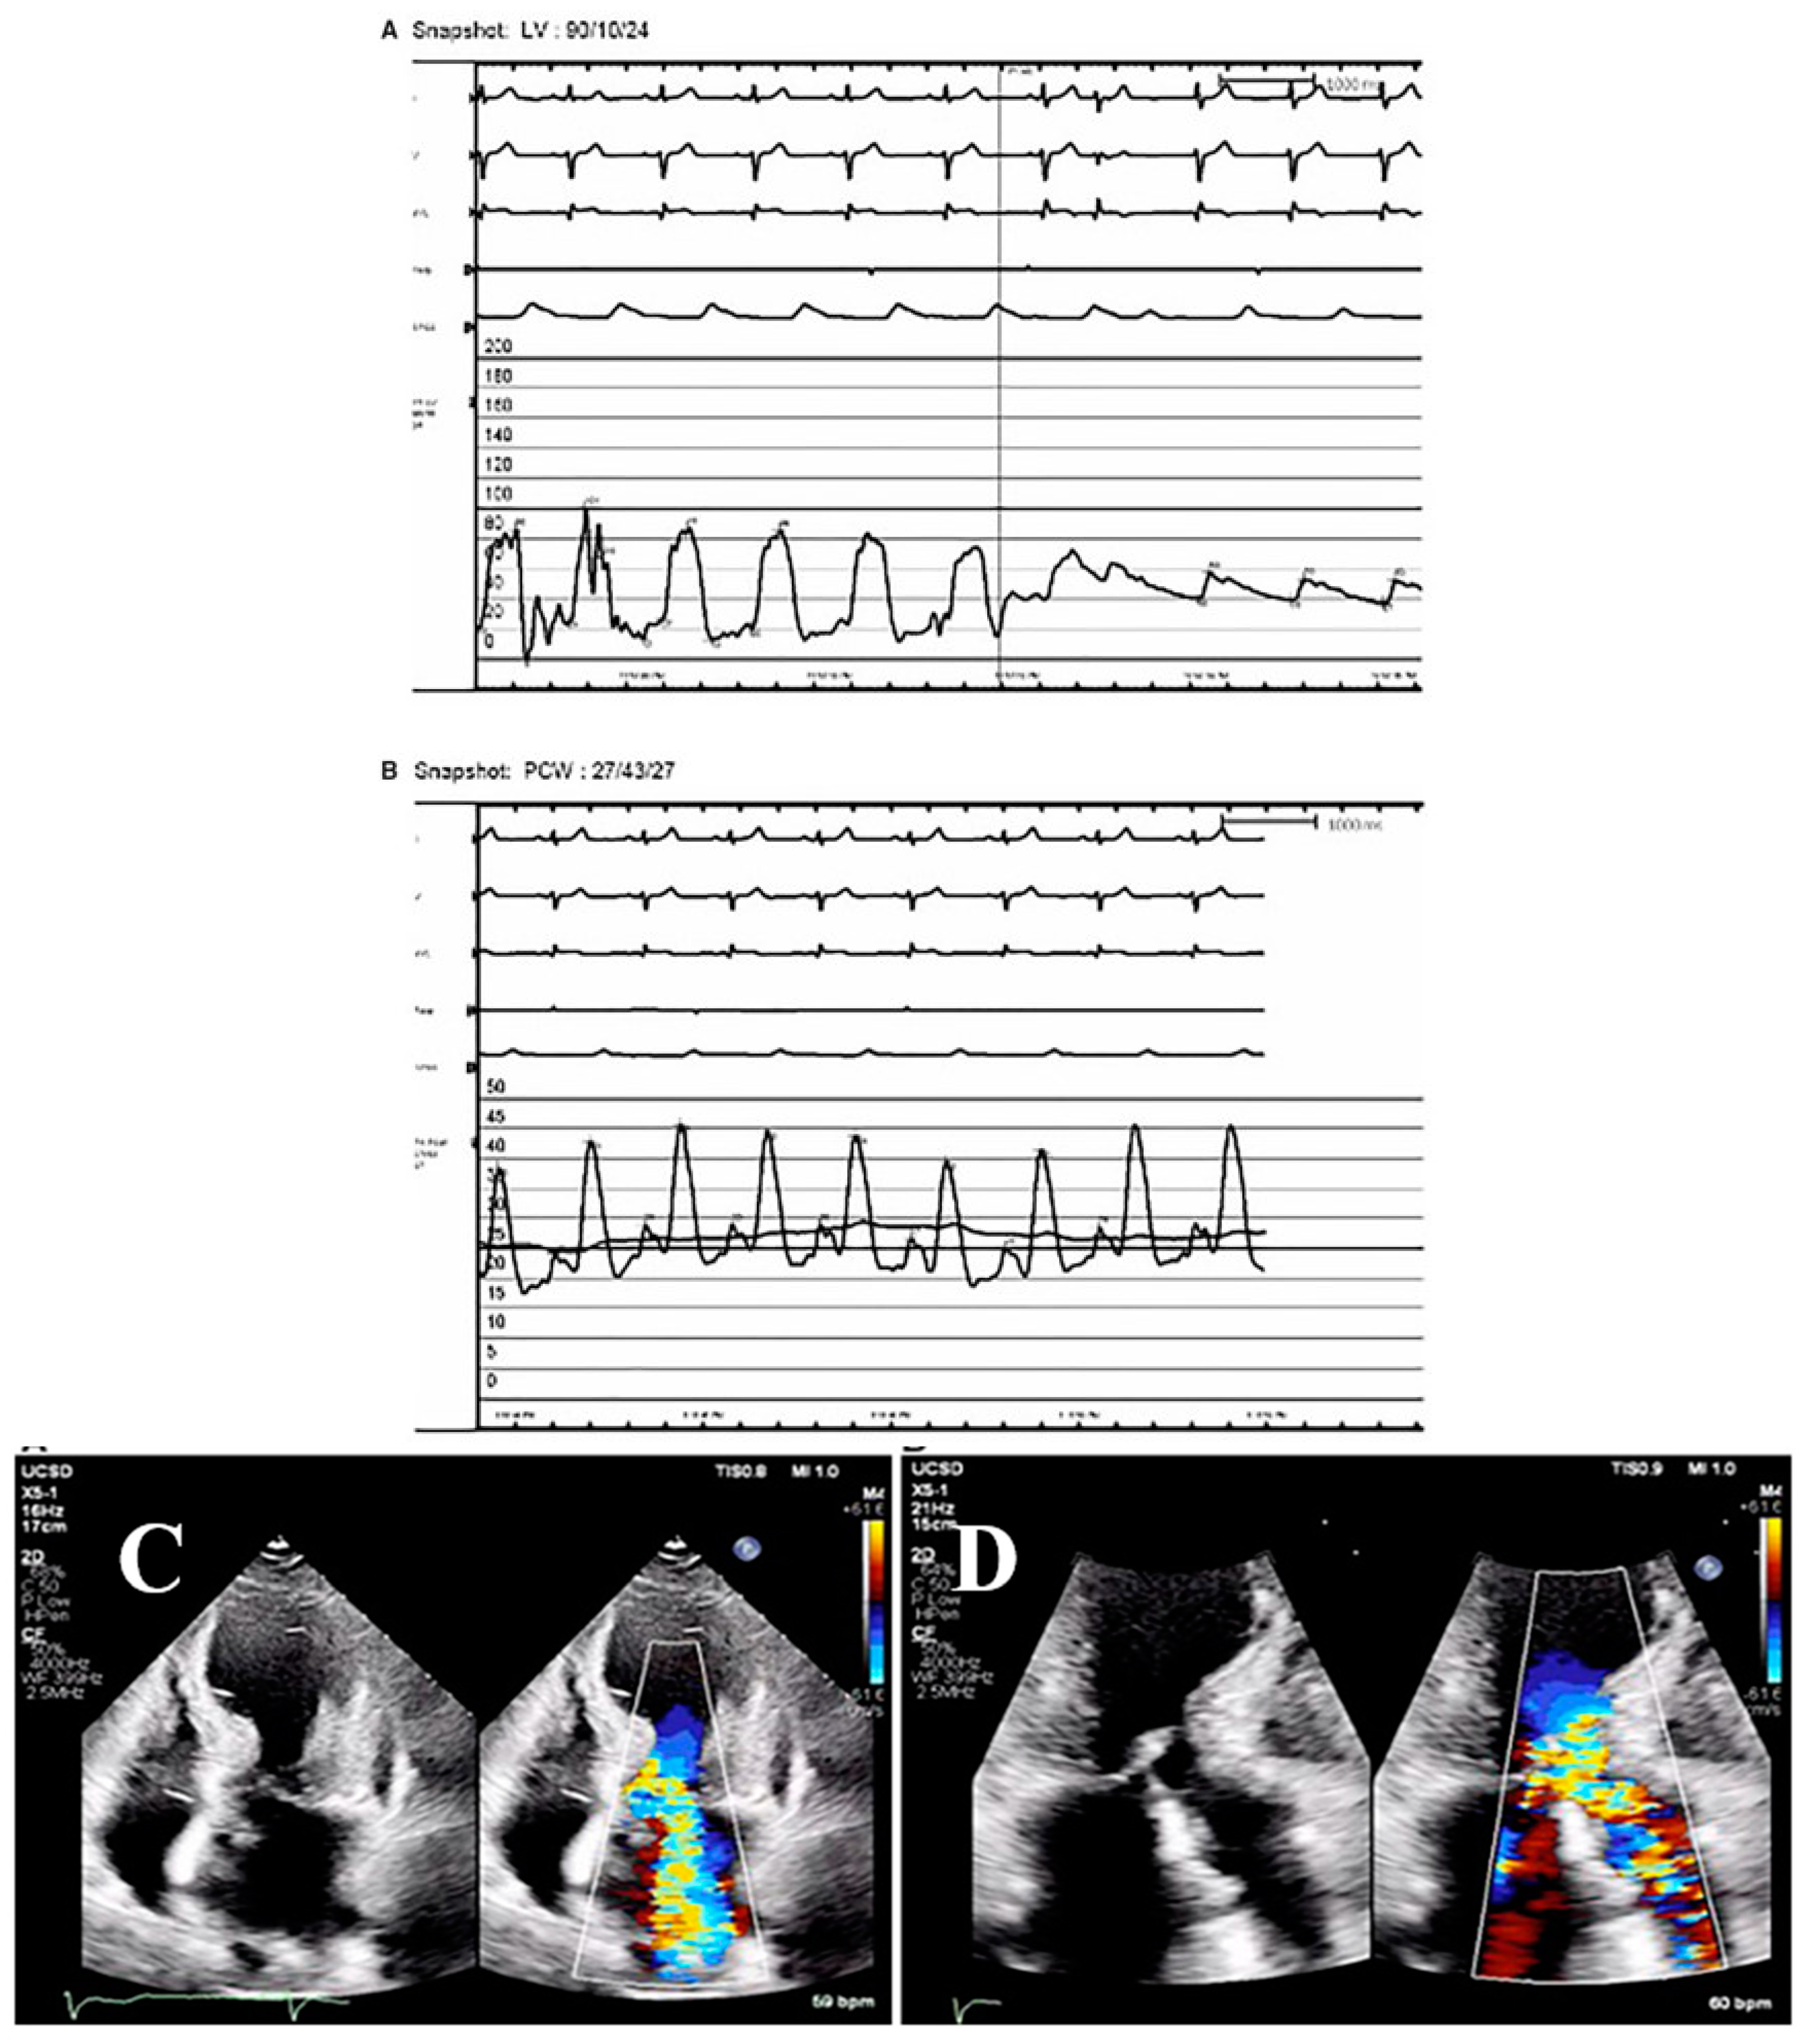

3.5. Hypotension in Patients with TTS

3.9. Left Ventricular Outflow Tract Obstruction in Patients with TTS

3.11. Mitral Regurgitation in Patients with TTS